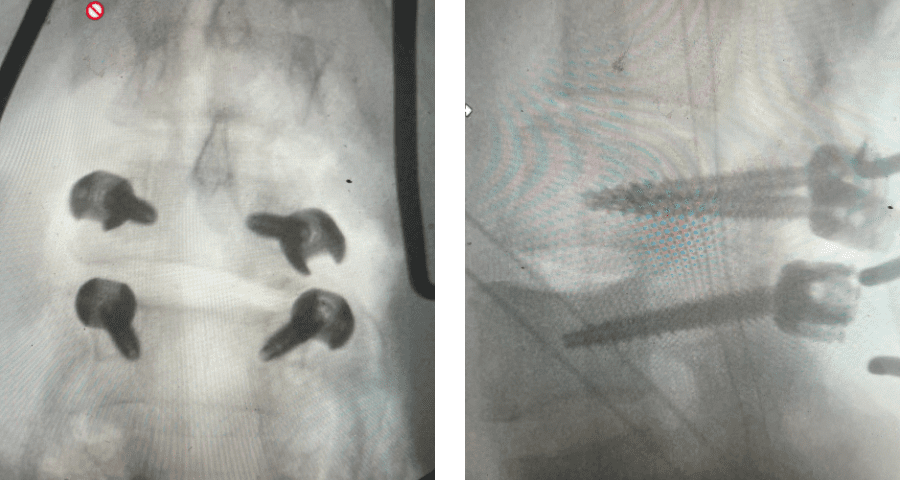

Here is a dramatic example of a patient who had prior laminectomy and fusion surgery four years earlier, and now presents with low back pain with severe burning pain in her right lower extremity pain. She did not respond to epidural steroids. She had a prior L3-S1 laminectomy, and an L3-5 instrumented fusion. A current MRI (Fig 4) demonstrated severe L2-3 next segment stenosis due the development of massively hypertrophied or enlarged L2-3 joint complexes. There was also a grade 1 retrolisthesis of L2 on L3 with a large anterior disc osteophyte complex. The configuration of the stenosis was worse in the right lateral recess secondary to the anterior osteophyte and more right-sided facet compression of the thecal sac, correlating with the patient’s right-sided symptoms. When the anatomy correlates with the patient’s symptoms that is the best set up for success. It was decided to offer a revision surgery to the patient, who agreed.

Revision surgery is more involved than primary surgery. In order to start decompressing this large complex, you must develop a plane; you have to find the edge of sometimes a remnant of a lamina or the lamina that can be buried in scar. You must carefully dissect the edge with a sharp upbiting curette and then either using a sharp Leksell to start removing this lamina or use a fine Kerrison to widen the plane and exposure and begin to expose the normal ligamentum above. In this case it was critical to expose and decompress the L3 nerve roots bilaterally. What is quite helpful is finding the inferior edge of the L2 facets. Then one must lift up the inferior L2 process up with a curette and simultaneously insert a Kerrison into joint space and remove the whole facet process. This is a great move because it allows access to the plane between the superior facet and the descending nerve root and a starting point to fully decompress the nerve root. Because of scarring there often is not a clear plane in order to accomplish the decompression. Care is taken to make sure there is a clear separation between edge of bone and dura during the process of inserting a Kerrison edge. The important part of this is feeling your opening and actually using your Kerrison as a dissecting tool once an edge has been established to perform a foraminotomy. We were able to remove the inferior L2 facet process with impunity as we knew we were performing an instrumented fusion to L2. The patient’s had a prior L3-5 instrumented fusion which upon exploration was solidly fused. It was decided to remove her prior hardware as it served its purpose and add a short segment from L2-3 (Fig 5). Patient did well after her surgery with relief of her right leg pain.

Fig 5: intraoperative fluoroscopic images demonstrating L2-3 screw placement.